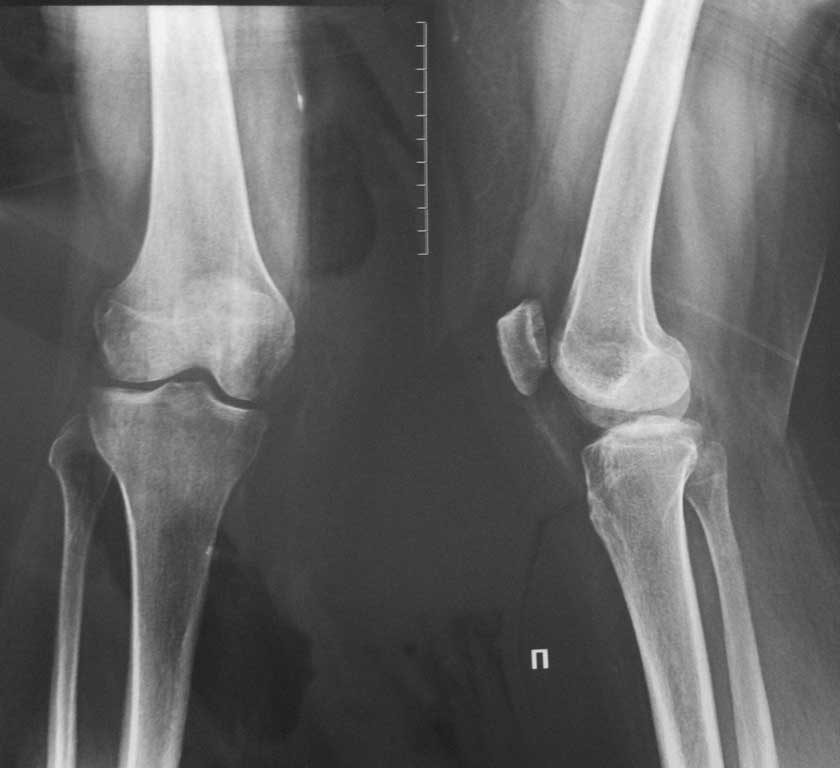

Спасибо Батал. отправляю снимки коленного сустава.

К сожалению, по этим снимками, относительно поставленной задачи, сказать мало что можно! Для оценки деформации правой нижней конечности нужен снимок всей конечности: от тазобедренного до голеностопного суставов! Тогда, на оснований нехитрых измерений, можно сказать на каком уровне имеет место деформация и имеется ли вообще та самая искомая деформация! Можно выполнить снимки правой нижней конечности по сегментам (тазобедренный сустав с максимальным захватом бедра, колено с максимальным захватом голени и лучше с захватом голеностопного сустава), далее соединить их воедино (тип сделать коллаж)!

А еще бы лучше - коленки плотно вместе и обе конечности рядом на одной пленке.